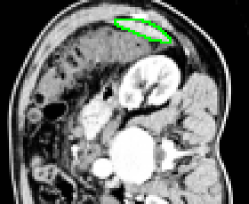

4.1 Metrication artifacts and minimal surfaces

We begin by comparing the CCMF segmentation result with the classical max-flow algorithm (graph cuts). Figure 3 shows the segmentation of a brain, in which the contours obtained by graph cuts are noticeably blocky in the areas of weak gradient, while the contours obtained by both AT-CMF and CCMF are smooth.